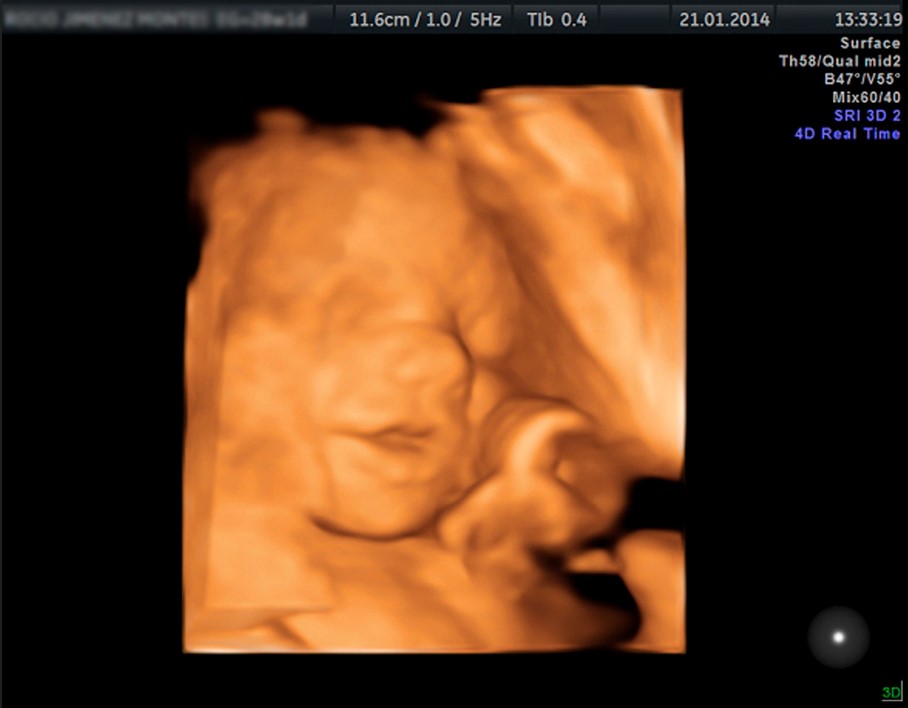

El embarazo es una etapa única, llena de emociones y cambios. En Viamed Salud, estamos aquí para acompañarte con información clara, seguimiento médico especializado y consejos prácticos que te ayudarán a vivir esta experiencia con confianza y bienestar.

Fundador equipo Diagnóstico y ginecología prenatal